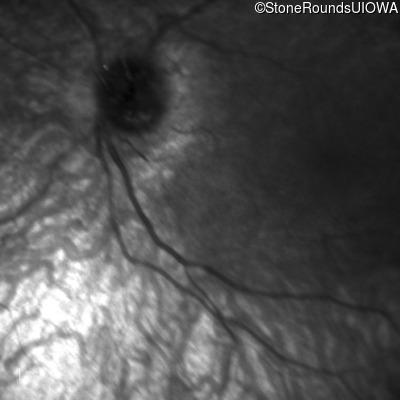

Infrared Fundus Photograph - Right -

Light Perception

Infrared Fundus Photograph - Left -